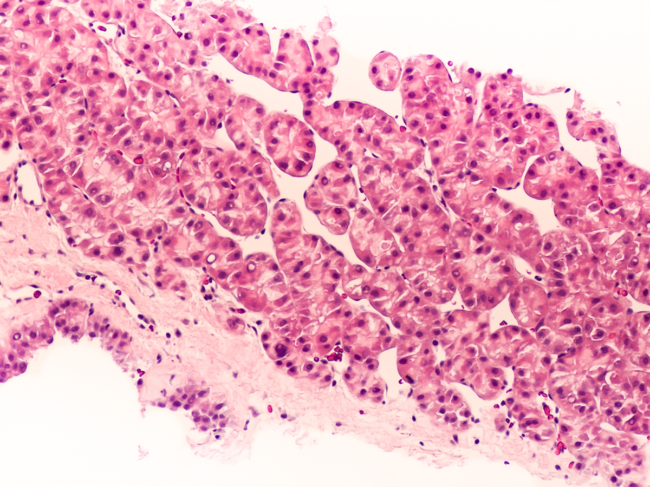

Photomicrograph of hepatocellular carcinoma

EWSAT1 as novel prognosis marker and therapeutic target for hepatocellular carcinoma

Researchers from Fudan University presented data from a study that aimed to assess the significance of a newly found long noncoding RNA (lncRNA), Ewing sarcoma-associated transcript 1 (EWSAT1), in hepatocellular carcinoma (HCC) metastasis. Read More